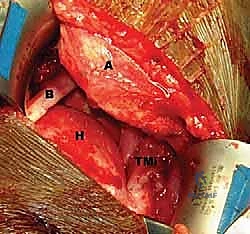

Identifying the Latissimus Dorsi and Teres Major:

- We'll identify the posterior border of the deltoid and retract it superiorly. Deep to this, we will find the latissimus dorsi and teres major muscles. The latissimus dorsi is typically more superficial and inferior to the teres major at this level.

- Surgeon's Directive: "Now, identify the interval between the deltoid and the underlying structures. We're looking for the characteristic fibers of the latissimus and teres major. Feel the muscle bellies – the latissimus is broad and flat."

FIG 4 • A. Incision for latissimus dorsi transfer, extending from the posterior axillary fold to the posterior acromion.

Dissection of the Latissimus Dorsi Tendon and Humeral Insertion:

- Carefully dissect along the superior border of the latissimus dorsi, separating it from the teres major tendon. This is where we need to be acutely aware of the neurovascular structures.

- Surgeon's Directive: "Let's use our blunt dissection here initially, then sharp dissection as needed. We're working towards the humeral insertion. Remember the 180-degree twist of the latissimus fibers."

- Crucial Step: Identify the conjoined tendon if present (30% of cases). If so, carefully separate the latissimus from the teres major using sharp dissection.

- Surgeon's Directive: "Maintain constant awareness of the radial nerve. It lies anterior to the latissimus. We'll internally rotate and adduct the arm to increase its distance from our working field, but we must protect it throughout this release."

- We will release the latissimus dorsi tendon from its humeral insertion. I prefer to leave a small cuff of tendon on the humerus for later closure if possible, but the priority is a clean release.

FIG 4 • B. The latissimus dorsi (L) is identified and separated from the teres major (TMa).

FIG 4 • C. The latissimus dorsi tendon is released from its humeral insertion.